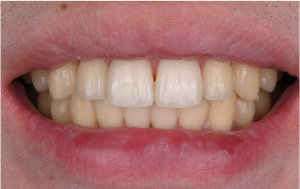

※口元の拡大

口元の印象も、自然でバランスの取れた状態となりました。

※術前、矯正治療期間中、術後

歯並びや歯の形が整うことで、口元の印象が変化することがわかります。